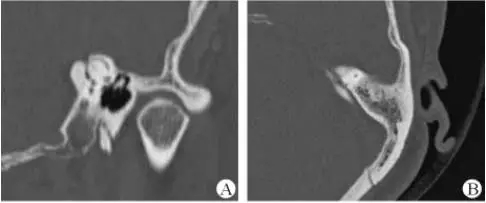

医生若怀疑此病将会安排内耳CT扫描。在大多数案例中,一旦此病被耳鼻喉科医生或其它听力健康专家确诊,则可实行手术治疗。外科手术风险包含听力损失以及神经损伤;重建及复原需内耳的治疗以及大脑的重塑。

幸运地是,医生在耳部检查的时候能看到珍珠白样的聚集物。大部分的胆脂瘤能通过外科手术移除。若不处理,胆脂瘤将长大并漫延侵润,造成内耳结构的永久性破坏导致眩晕以及平衡问题或面部神经以及肌肉的破坏,造成麻痹。